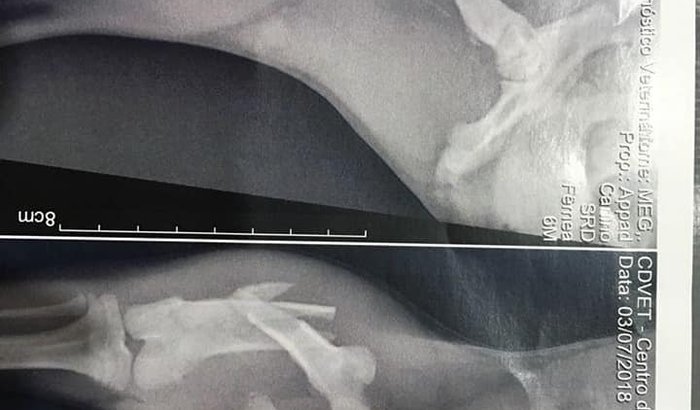

Resgatamos essa menina domingo, percebemos que estava com a pata machucada e levamos para um local seguro, ontem ela fez um raio-x que confirmou o que tanto tememos, uma fratura super grave, como podem ver na foto. Agora ela precisa passar por uma cirurgia de urgência porque essas pontas dos ossos que vocês estão vendo podem romper as veias e artérias que passam ali. O Dr Ricardo Requena da clínica espaço animal que sempre nos ajuda vai cobrar o valor de R$1.200,00 que inclui exame de sangue, anestesia inalatória, internação até sábado e a colocação de placa e parafusos bloqueados. Precisamos arrecadar esse valor para poder pagar a cirurgia. Gente, sabemos que não está fácil pra ninguém, mais se cada um ajuda com um pouquinho além de não pesar pra ninguém ainda conseguimos salvar uma vida. Ficaremos eternamente gratos com a ajuda que vier, a doação pode ser feita por depósito bancário, pode ser deixado direto na clínica ou podemos ir buscar.